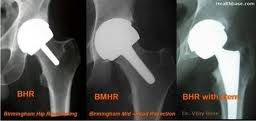

An alternative to total hip replacement (THR) is hip surface replacement (HSR), also referred to as hip resurfacing. With both THR and HSR, a prosthetic socket is pressed into the pelvis. With THR, the end of the femur is amputated, a metal shank is inserted into the femur, and the shank holds a ball which mates with the socket. With resurfacing, the end of the femur is not amputated; the outer surface of the femoral ball is replaced with a cylindrical metal cap. Resurfacing eliminates the common THR problem of the metal shaft loosening from the femur. Resurfacing preserves bone stock if a revision is ever needed. A larger diameter ball and socket more closely mimic the natural joint structure, reducing the risk of dislocation and improving range of motion. There has been no published clinical evidence to show that today’s CoCr metal-on-metal articulating surfaces have the osteolytic effect on bone that earlier polyethylene devices had. Ten year success rates of hip resurfacing from studies in England report success equal to or greater than standard total hip replacement, in age-matched patients. In the United States, the first modern resurfacing device received FDA approval in May 2006, while some 90,000 resurfacings have been performed world-wide.